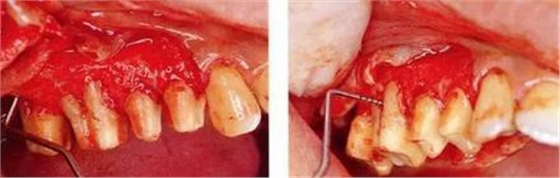

▼圖16-1 ▼圖16-2

圖16-1對(duì)右上6.7分叉部病變處理時(shí),對(duì)包括右上4.5進(jìn)行齦瓣分割,確認(rèn)骨缺失狀態(tài)。右上7頰側(cè)存在著12mm的骨緣下缺失。

圖16-2右上6水平的分叉部病變到達(dá)了III度。